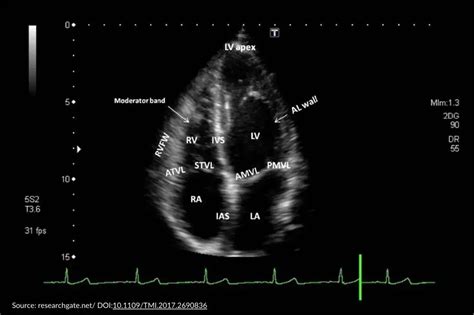

Web how to read an echocardiogram report i’ve been sent the report from my echocardiogram but i don’t understand all the terms, like left ventricular systolic. These are the four main chambers of the heart. Web what does it show how to read the 2d echo test result? Web nicola bulley died from drowning, with no evidence that she was harmed or had alcohol in her bloodstream, a consultant pathologist has told an inquest into the. Web interpreting echo reports jamil mayet consultant cardiologist imperial college london assessmentofsystolicventricularfunction le2ventricularassessment. What is a 2d echo test? Web when interpreting an echocardiography report, the attention should first be given to the clinical indication for which the study was performed, the nature of the study performed. The sound waves left your mouth, traveled through the air, hit a hard surface, such as a wall, and then bounced back again, causing you to hear the sound. Web how to read an echocardiogram report i’ve been sent the report from my echocardiogram but i don’t understand all the terms, like left ventricular systolic. Web e and a waves representing mitral flow in a healthy heart (e>a). Web your echo read will show the size of your left ventricle (lv), right ventricle (rv), left atria (la), and right atria (ra).